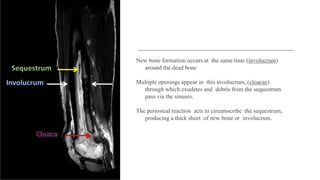

New bone formation occurs at the same time (involucrum)

around the dead bone

Multiple openings appear in this involucrum, (cloacae)

through which exudates and debris from the sequestrum

pass via the sinuses.

The periosteal reaction acts to circumscribe the sequestrum,

producing a thick sheet of new bone or involucrum.